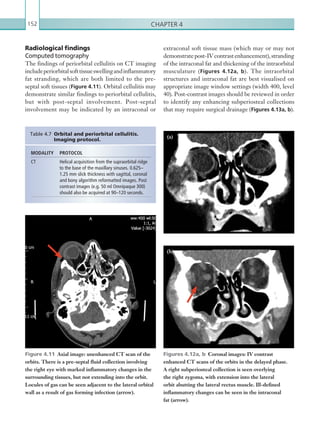

associated finding.

Complications of acute cholecystitis include

abscess formation, pericholecystic fluid collections,